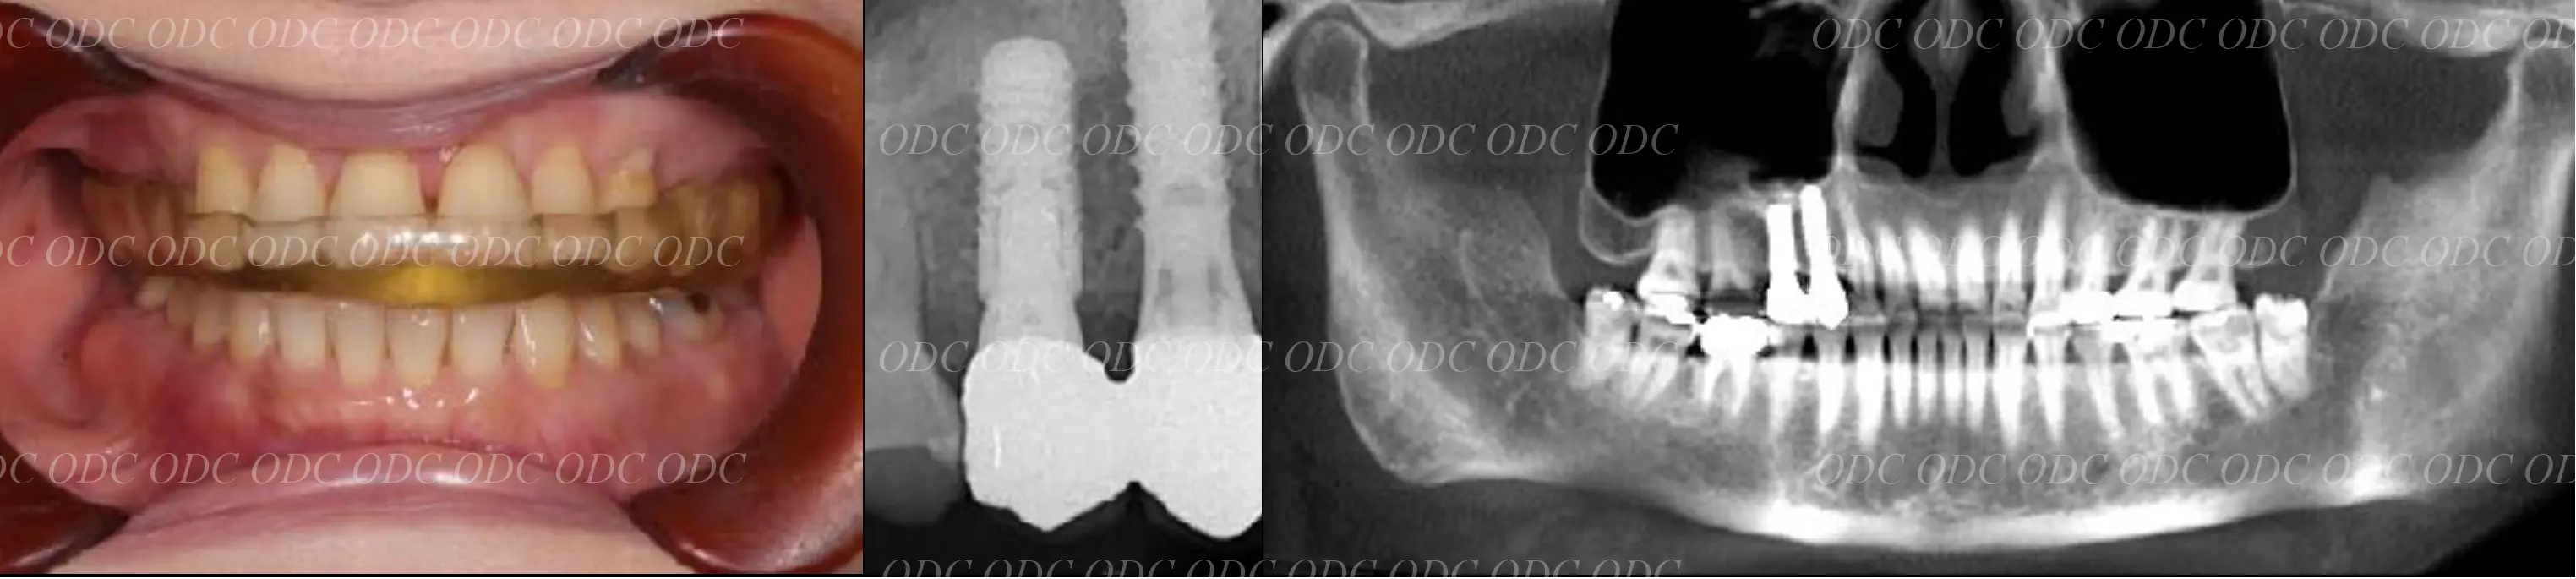

2014年、治療終了時の口腔内の状態です。

インプラント上部構造はCADCAMによって作成されたジルコニアの上部構造です。

2024年、治療終了後約10年が経過いたしました。

顎関節を考慮した包括的な治療を行うことで咬合状態(噛み合わせ)は現在もとても安定した状態です。